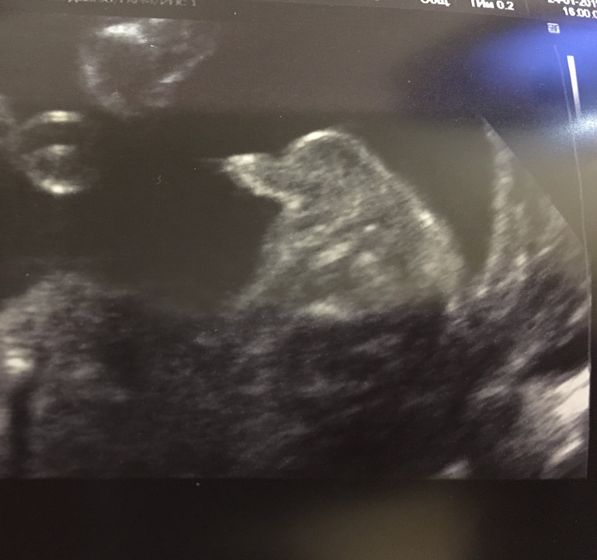

Второй скрининг на сроке 21 и 3 подтвердил мальчика?

?? Он нам с мужем всего себя полностью показал, не дергался, лежал как на диване? Вес: 401 грамм. ? Остальное все хорошо, единственное двухдолевая плацента, но это никак ни на что не повлияет! До первого скрининга отставала на 3-4 дня от акушерского, на 1 скрининге перегнала акушерский на 1 день, на 2 скрининге отстала на 3 дня от акушерского (от 1 скрининга минус 4 дня), врач сказал что малыш по прогнозам крупным к родам не будет, около 3-ех кг.

Фотка писюна на память, ну и меня на 21 недельке?